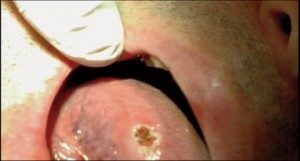

Certain diode lasers are FDA approved to help treatment of TMD and facial muscle pain. Diode laser can actually penetrate tissue and increase blood flow, decrease edema, and aide in healing. Although diode lasers have been used for many years in treating muscle and joint pain, this could provide another avenue in treating our patients. Diode lasers have been used to help treat periodontal disease and certain studies have shown better results and advantages of utilizing a diode laser in conjunction with scaling and root planning. These studies have shown reduction in bleeding on probing and reduced pocket depth. Other uses for diode laser include treating aphthous ulcers, desensitizing teeth, pulpotomy procedures and, best of all, removing inflamed excess tissue that makes taking your crown impression impossible.